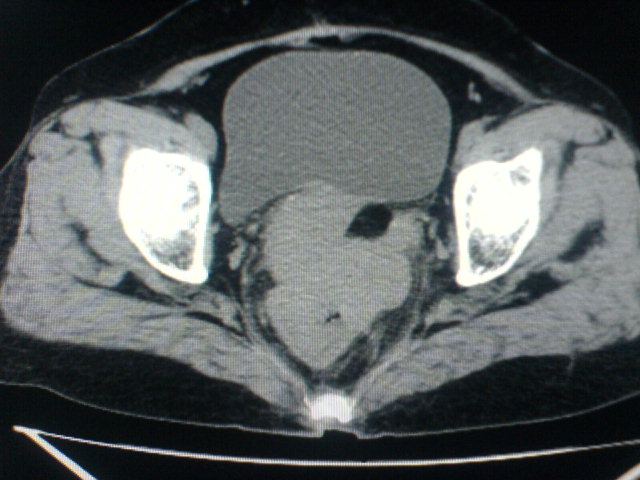

患者为老年女性,肿块最大层面不是位于宫颈,但宫颈偏后方有一囊状低密度影,肿块主要位于乙状结肠及直肠,所以考虑乙状结肠及直肠癌浸犯宫颈可能性大。

患者女性60岁 病史不详

宫颈癌侵犯直肠可能

考虑子宫内膜癌浸犯直肠。

考虑直肠癌侵及宫颈可能;建议增强扫描。

支持考虑宫颈癌上下前后通吃

考虑:直肠及乙状结肠癌侵及宫颈,囊性转移(假性粘液瘤)

支持宫颈癌侵犯直肠。

考虑直肠及乙状结肠癌侵犯邻近结构。